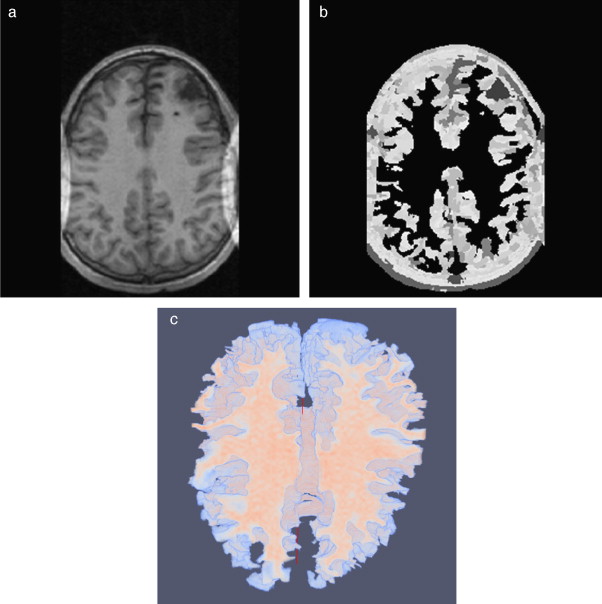

4.3. Caso 3: filtrado de difusión anisotrópica y segmentación Region Growing - BrainWeb

En este caso, se corrompió el volumen phantom con ruido aditivo gaussiano y se procedió a aplicar las rutinas de filtrado y segmentación. Para suavizar el ruido de la imagen, se aplicó la rutina de filtrado con difusión anisotrópica (sección 2.2.1) y la segmentación de la zona de la materia blanca fue realizada con la rutina Region growing (sección 2.3.2). El flujograma de técnicas empleadas es similar al presentado en la figura 21 .

En la figura 27 se presentan los resultados obtenidos al segmentar la zona de la materia blanca con las rutinas y mencionadas. En la figura 27 .a se presenta la imagen phantom original, mostrando el corte axial número 98 del phantom . En la figura 27 .b se presenta la imagen phantom con ruido aditivo gaussiano. En la figura 27 .c es mostrada la imagen resultante luego de filtrar (b) con el filtro de difusión anisotrópica, además se observan las 5 semillas (seed points) seleccionadas de manera arbitraria sobre el área de la materia blanca. Las semillas empleadas tenían forma esférica de 2 pixels de radio, con el centro en las coordenadas X,Y,Z , las coordenadas de las semillas son: Seed1= (65,59,98), Seed2 =(112,55,98), Seed3 =(117,104,98), Seed4 =(127,137,98), Seed5 =(55,128,98). En la figura 27 .d se presenta el resultado de la segmentación (en rojo). En la figura 27 .e se presenta la zona de la materia blanca proporcionada por BrainWeb.

Materia blanca segmentada en volumen phantom. (a) Corte axial número 98 de ...

Figura 27.

Materia blanca segmentada en volumen phantom . (a) Corte axial número 98 de imagen de phantom original. (b) Imagen original con ruido gaussiano agregado (c) Imagen con ruido filtrada con filtro de difusión anisotrópica. (d) Materia blanca segmentada con algoritmo Region Growing con 5 semillas esféricas. (e) Zona de la materia blanca segmentada por BrainWeb .